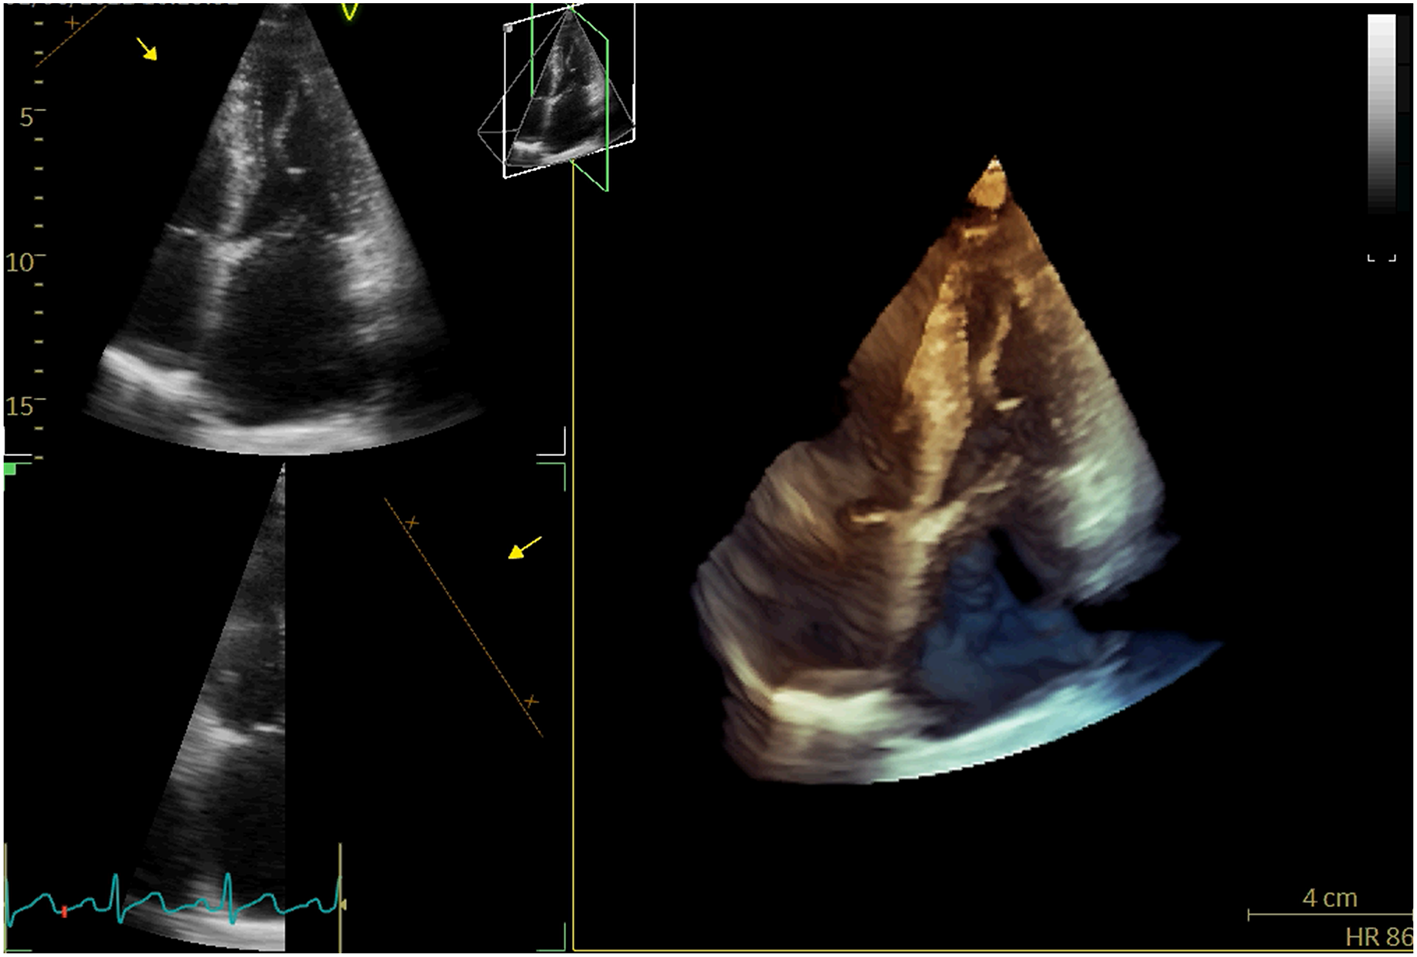

A 71-year-old woman repeatedly presented to the outpatient department for cough, whitish sputum, and progressive shortness of breath (SOB) since 2018. Physical examination indicated that vital signs were stable (BP: 124/71 mmHg, Temperature: 37.0°C, P: 70 beats/min, SPO2: 98%), and lower limb edema. ECG: normal. Cardiac enzyme: unremarkable. Chest X-ray: bilateral lower zone haziness, blunted bilateral costophrenic angle. The symptoms were resolved after treatment with augmentin, Lasix, and oxygen treatment (2L/min). Subsequent transthoracic echocardiography (TTE) and transesophageal echocardiography (TEE) showed that normal-sized left ventricle with preserved LVEF (55–60%); severe anterior directed MR due to prolapse P2 and P3 segment. She underwent Neochord repair with 4 artificial chords implanted, residual trivial MR with a mean trans-mitral gradient of 4 mmHg. The patient followed a regular postoperative valvular evaluation by TTE every 6 months after being discharged from the hospital. Twenty-four months after discharge, she was admitted to the cardiac clinic again for a severe SOB and heart failure symptoms (New York heart association functional class 3–4) and decreased exercise tolerance. Conventional and 3-D TTE showed severe anterior directed MR due to the detached artificial chords (Figure 1).

Figure 1

3D-TTE revealed detached artificial chords.